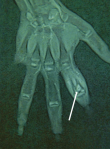

Diagnostic assessment: laboratory investigation revealed a normal complete blood count, with slightly elevated C-reactive protein (CRP) levels at 15 mg/L (normal value < 6 mg/L), and an elevated erythrocyte sedimentation rate (ESR) of 20 mm/h (normal value < 10 mm/h). An anteroposterior and lateral radiographs of the hand showed an oblique osteolytic lesion of the cortex and the medullary space in the head and neck of the proximal phalanx of the index finger (Figure 1). An MRI of the hand showed a corticomedullary lesion in the metaphyseal-epiphyseal region of the first phalanx of the index finger, with a punctate osseous focus and significant perilesional edema, consistent with osteoid osteoma (Figure 2).

Figure 2: magnetic resonance imaging coronal image of the hand revealing a well-defined corticomedullary lesion in the metaphyseal-epiphyseal region with a punctate osseous center, cortical erosion at the articular surface, and associated bone marrow edema (white arrow)